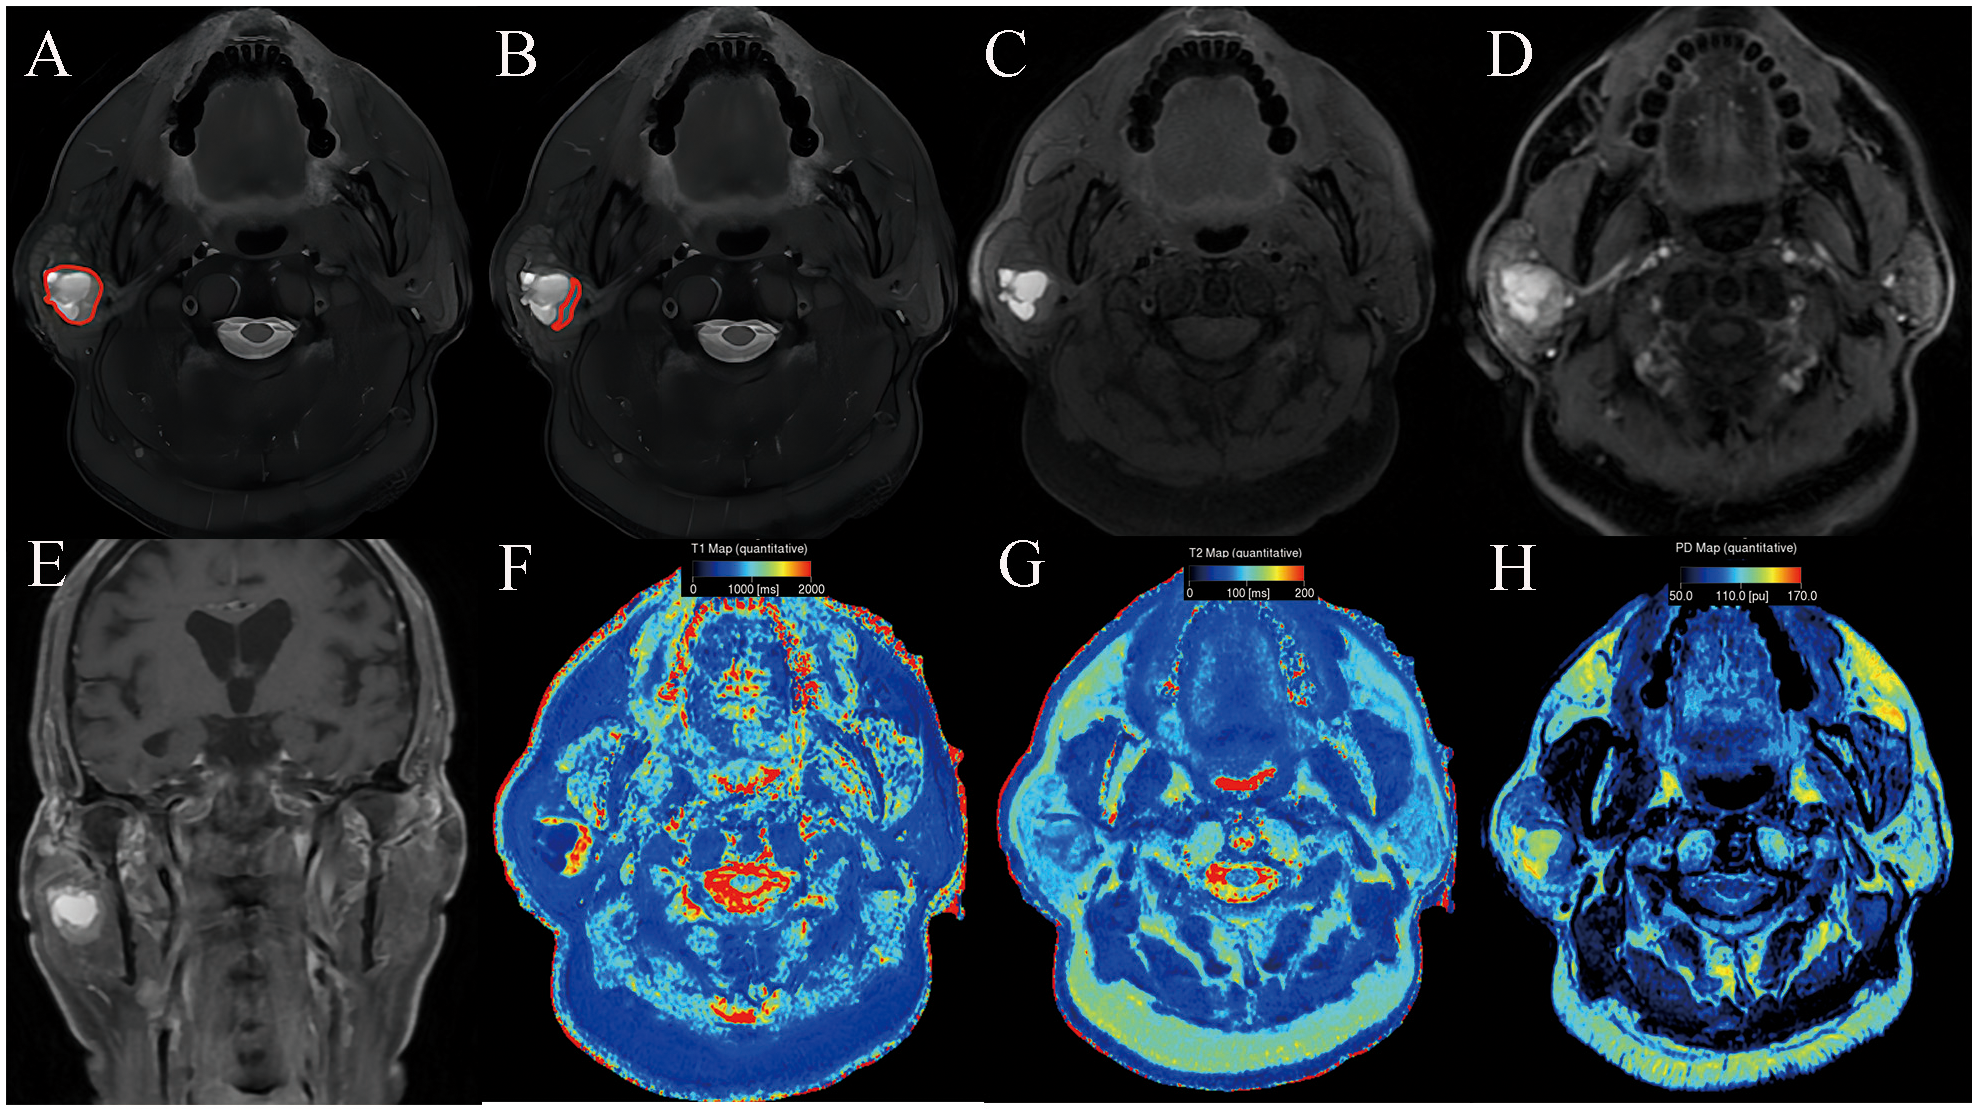

Table 3 summarizes SyMRI’s quantitative parameters for PA and WT. The T1, T1sd, T2, PD, T1ratio, T2ratio, and PDratio of PA derived from full-lesion ROI were significantly higher than those of WT (P < 0.05). The T1, T1sd, T2, T2sd, PD, PDsd, T1ratio, T2ratio, and PDratio of PA derived from partial-lesion ROI were significantly higher than those of WT (P < 0.05) (Figures 1, 2). In terms of T2sd and PDsd derived from full-lesion ROIs, there were no significant differences between PA and WT (P > 0.05). The T1, T2, and PD values measured on the masseter muscle did not differ significantly between the two types of lesions (P > 0.05).

Figure 1. Pleomorphic adenoma of the parotid gland in a 42-year-old male subject. The ROI delineation methods included the largest area of the largest section (full lesion, A) and the solid portion within the largest section (partial lesion, B). On conventional MRI, this mass showed hyperintense on T2WI (A, B), a well-defined border (C), and marked enhancement on contrast enhanced T1WI (D, E). In comparison with WT, it demonstrated significantly higher SyMRI-derived quantitative parameters for partial-lesion ROI (T1: 2077 ms; T1sd: 529 ms; T2: 90 ms; T2sd: 13 ms; PD:99 pu; PDsd: 8.4 pu) on axial T1 mapping (F), T2 mapping (G), and PD mapping (H).